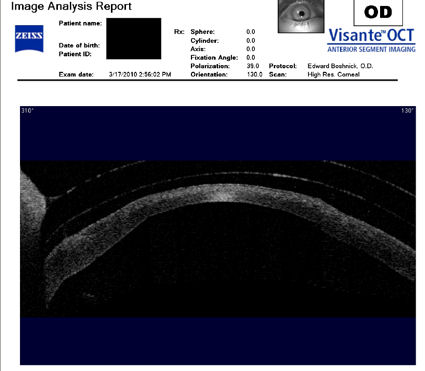

Следующие изображения были получены с использованием метода, называемого оптической когерентной томографией, или ОКТ. Прибор позволяет получить изображение в поперечном сечении путем сканирования передней части глаза (переднего сегмента) лучом света. Думайте об этом как об ультразвуке, использующем свет вместо звуковых волн для создания изображения живых тканей.

На изображении ниже представлен снимок роговицы в поперечном сечении после операции LASIK. Белая изогнутая линия вверху - это передняя поверхность твердой контактной линзы. Следующая едва заметная белая линия - это задняя поверхность линзы. Следующая область, которая имеет зернистый вид, - это пространство между хрусталиком и роговицей, заполненное физиологическим раствором. Роговица имеет классические признаки эктазии - истончение, выпуклость и неправильную форму.

Изображения любезно предоставлены доктором Эдвардом Бошником, который посвятил свою практику восстановлению качественного зрения и информации о эктазия после операции LASIK .